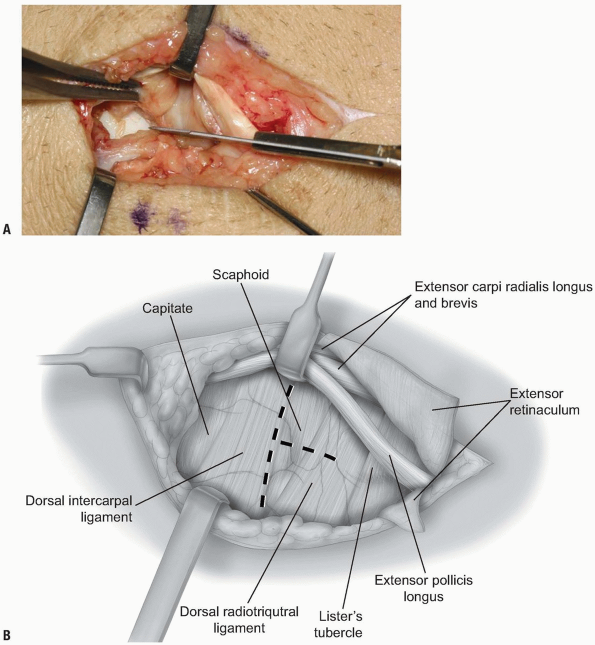

overlying the 3rd dorsal compartment is incised longitudinally from the

deep antebrachial fascia proximally and then distally to the distal

margin of the retinaculum (Fig. 1-6).

The EPL in the 3rd dorsal compartment is retracted radially, and the

4th extensor compartment is elevated subperiosteally or by dividing the

septum between the 3rd and 4th compartments and reflecting the

retinaculum as an ulnarly based flap (Fig. 1-7).

The approach is limited by the septum between the 5th and 6th dorsal

compartments. Radially, the extensor retinaculum may be elevated off of

Lister’s tubercle and the 2nd dorsal compartment released.

Subsequently, the extensor carpi radialis brevis (ECRB) and extensor

carpi radialis longus (ECRL) can be retracted radially deep to the

extensor retinaculum, with the EPL retracted radially and superficial

to the extensor retinaculum. This allows for exposure of approximately

90% of the dorsal wrist (2) (Fig. 1-8).

FIGURE 1-7 A,B:

The EPL in the 3rd dorsal compartment is retracted radially, and the 4th extensor compartment is elevated subperiosteally or by dividing the septum between the 3rd and 4th compartments and reflecting the retinaculum as an ulnarly based flap. |

![]() |

|

FIGURE

1-8 The ECRL can be retracted radially deep to the extensor retinaculum, with the EPL retracted radially and superficial to the extensor retinaculum. This allows for exposure of approximately 90% of the dorsal wrist. |

FIGURE 1-9 A,B:

The fibers of the dorsal radiocarpal and dorsal intercarpal ligaments are incised in line with their fibers in the midline of each ligament, with continuation along the dorsal rim of the radius toward the radial styloid process to generate a three-sided trapezoidal flap remaining attached on the radial side. The flap of capsule is then elevated sharply off the dorsal surface of the triquetrum then off the lunate and scaphoid, with care taken to avoid injury to the lunotriquetral and scapholunate interosseous ligaments. |